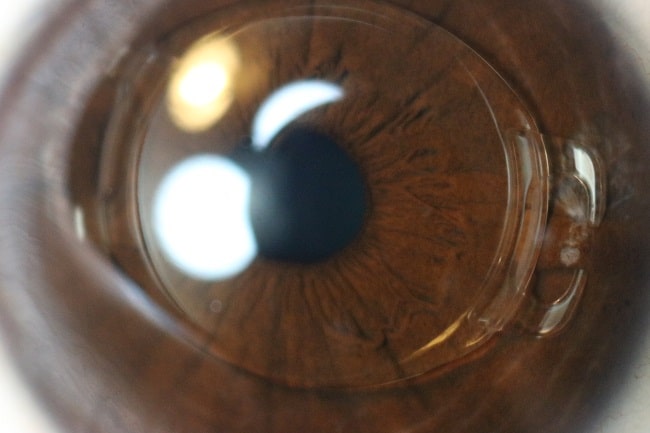

Pertama adalah anterior chamber phakic IOL (AC pIOL) yang diletakkan di bilik mata depan, yakni di antara kornea dan iris. Kedua, PC pIOL yang diletakkan di bilik mata belakang, yaitu di antara iris dan lensa mata (crystalline natural lens). Ada 2 jenis AC pIOL, yaitu angle support pIOL dan iris claw atau iris-fixated pIOL. Akan tetapi, saat ini angle support pIOL telah ditarik dari pasaran karena komplikasi yang ditimbulkan. Jenis lensa posterior pIOL yang ada di pasaran adalah implantable collamer lens dan implantable phakic contact lens (IPCL).[1,2]

Perbedaan phakic IOL dan IOL pada operasi katarak adalah dalam operasi katarak, lensa mata kristalin diambil lalu diganti dengan lensa tanam (IOL). Sementara, pada prosedur phakic IOL, lensa tanam diletakkan di depan lensa mata kristalin. Lensa mata kristalin tidak diangkat pada prosedur phakic IOL.[3]